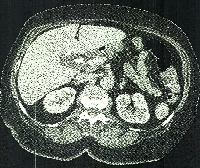

Πρόκειται για γυναίκα ασθενή 61 ετών η οποία, στα πλαίσια διερεύνησης αποφρακτικού ικτέρου, διαπιστώθηκε (MDCT, EUS+Bx) ότι έπασχε από αδενοκαρκίνωμα της παγκρεατικής κεφαλής. Η παγκρεατική μάζα διηθούσε την οπίσθια επιφάνεια της άνω μεσεντερίου φλέβας, αμέσως κάτω από τη σπληνομεσεντέριο συμβολή (εικόνα 1). Η ασθενής υποβλήθηκε σε επέμβαση Whipple’s, εκτομή και άμεση ανακατασκευή του τοιχώματος της πυλαίας φλέβας (clamp & sew), ηπατοδωδεκαδακτυλικό και αορτοκοιλικό λεμφαδενικό καθαρισμό (εικόνες 2, 3). Οι αναστομώσεις συμπεριλαμβάνουν διαγαστρική παγκρεατογαστροστομία (εικόνα 4), τελικοτελική γαστρονηστιδοστομία (τύπου Billroth I) και ηπατικονηστιδοστομία (εικόνα 5). Η ασθενής έλαβε εξιτήριο την 11η μετεγχειρητική ημέρα.